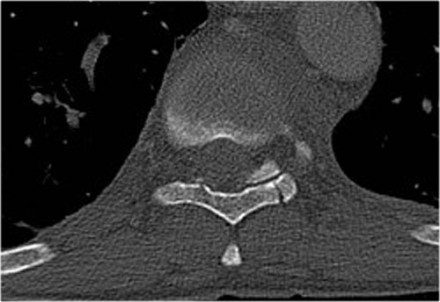

The image shows a vertebral fracture with a transverse fracture of the spinous process, but also a fracture of the sternum.

Analogous to the 3-column classification of Denis, some investigators

consider the sternum as the fourth column in upper thoracic spinal

fractures and recognize it as an independent variable in the assessment

and treatment of these patients (5).